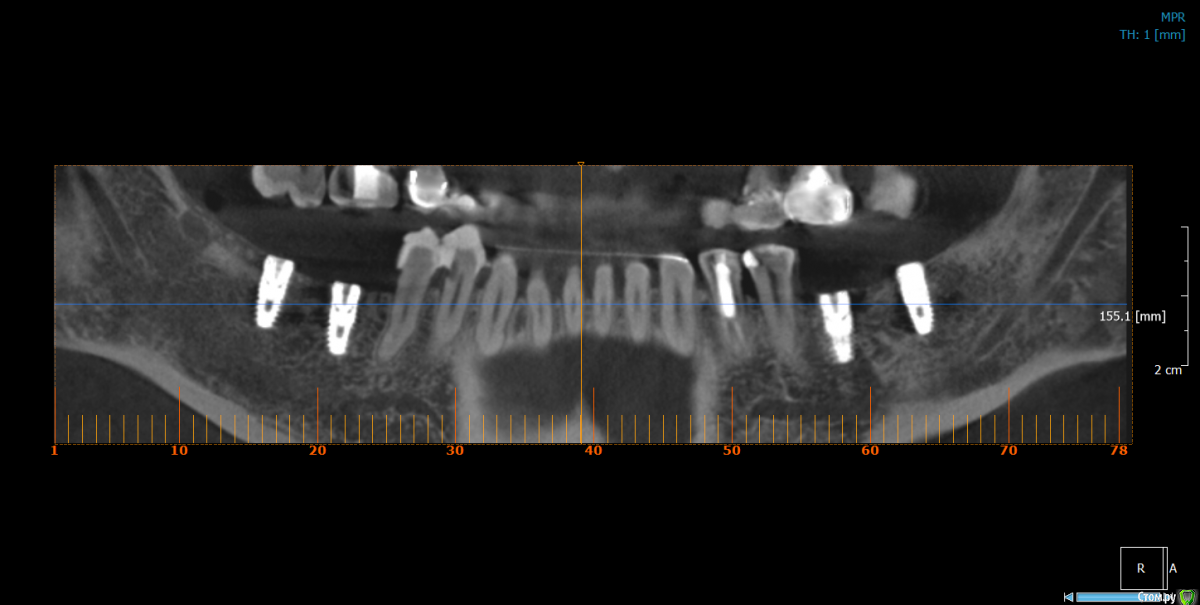

Популярный пост Dantist55 Опубликовано 22 декабря, 2014 Автор Популярный пост Поделиться Опубликовано 22 декабря, 2014 Через 5 месяцев... 21 Ссылка на комментарий

Mane Опубликовано 22 декабря, 2014 Поделиться Опубликовано 22 декабря, 2014 в целом хорошо. но нет деталей где я смогу понять что качественно отработали: 1) кт срезы до и после с замерами чтоб было понятно на сколько нарастили 2)кт срезы с установленными имплантами чтоб было понятно какие болты удалось установить и стало чтоб всем понятно для чего наращивали - ведь вы растили в высоту и в ширину. 3) фото на этапе установленных имплантов - соотношение платформы импланта и уровня кости - заглубили или нет - если да то насколько. Ориентировались ли на будущий зенит зуба. мне понравилось. но чуйка что есть гиперлечение - думаю можно было болты и костную пластику совместить. Растить по высоте я скорее всего бы не стал. 1 Ссылка на комментарий

Dantist55 Опубликовано 22 декабря, 2014 Автор Поделиться Опубликовано 22 декабря, 2014 в целом хорошо. но нет деталей где я смогу понять что качественно отработали: 1) кт срезы до и после с замерами чтоб было понятно на сколько нарастили 2)кт срезы с установленными имплантами чтоб было понятно какие болты удалось установить и стало чтоб всем понятно для чего наращивали - ведь вы растили в высоту и в ширину. 3) фото на этапе установленных имплантов - соотношение платформы импланта и уровня кости - заглубили или нет - если да то насколько. Ориентировались ли на будущий зенит зуба. мне понравилось. но чуйка что есть гиперлечение - думаю можно было болты и костную пластику совместить. Растить по высоте я скорее всего бы не стал.КТ посмотрю позже на работе - я в отпуске.По высоте добавляли чтобы зубы не получились большими.Импланты не заглублял, т.к. у XIVE полированная фаска.Насчет гиперлечения может Вы и правы. Эту работу я сделал сразу после приезда от Кури. 2 Ссылка на комментарий